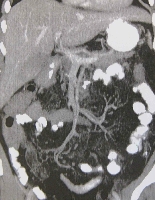

Πρόκειται για γυναίκα ασθενή 55 ετών η οποία, στα πλαίσια διερεύνησης αιμορραγίας ανώτερου πεπτικού, υποβλήθηκε σε απεικονιστικές εξετάσεις που ανέδειξαν οπισθοπεριτοναϊκό όγκο μεγέθους μεγαλύτερου των 20 cm, που εξορμούνταν από το δωδεκαδάκτυλο (εικόνα 1). Εγχειρητικά, εκτός από την εμπλοκή της 3ης & 4ης δωδεκαδακτυλικής μοίρας, διαπιστώθηκε ότι ο όγκος ενέπλεκε και τη μεσότητα του αριστερού ουρητήρα. Η παθολογοανατομική εκτίμηση του en bloc παρασκευάσματος (εικόνα 2) ανέδειξε την ύπαρξη GIST (80 μιτώσεις ανά 50 ΟΠ Χ 400). Η ανατομική αποκατάσταση πραγματοποιήθηκε με τελικο-τελική ουρητηρο-ουρητηροστομία (εικόνα 3) και πλαγιο-πλάγια δωδεκαδακτυλο-νηστιδοστομία (εικόνα 4). Η μετεγχειρητική αξονική τομογραφία ανέδειξε άθικτα μεσεντέρια αγγεία (εικόνα 5). Η ασθενής έλαβε εξιτήριο την 6η μετεγχειρητική ημέρα. Βρίσκεται σε αγωγή με Gleevec και εξακολουθεί να παραμένει ελεύθερη νόσου.